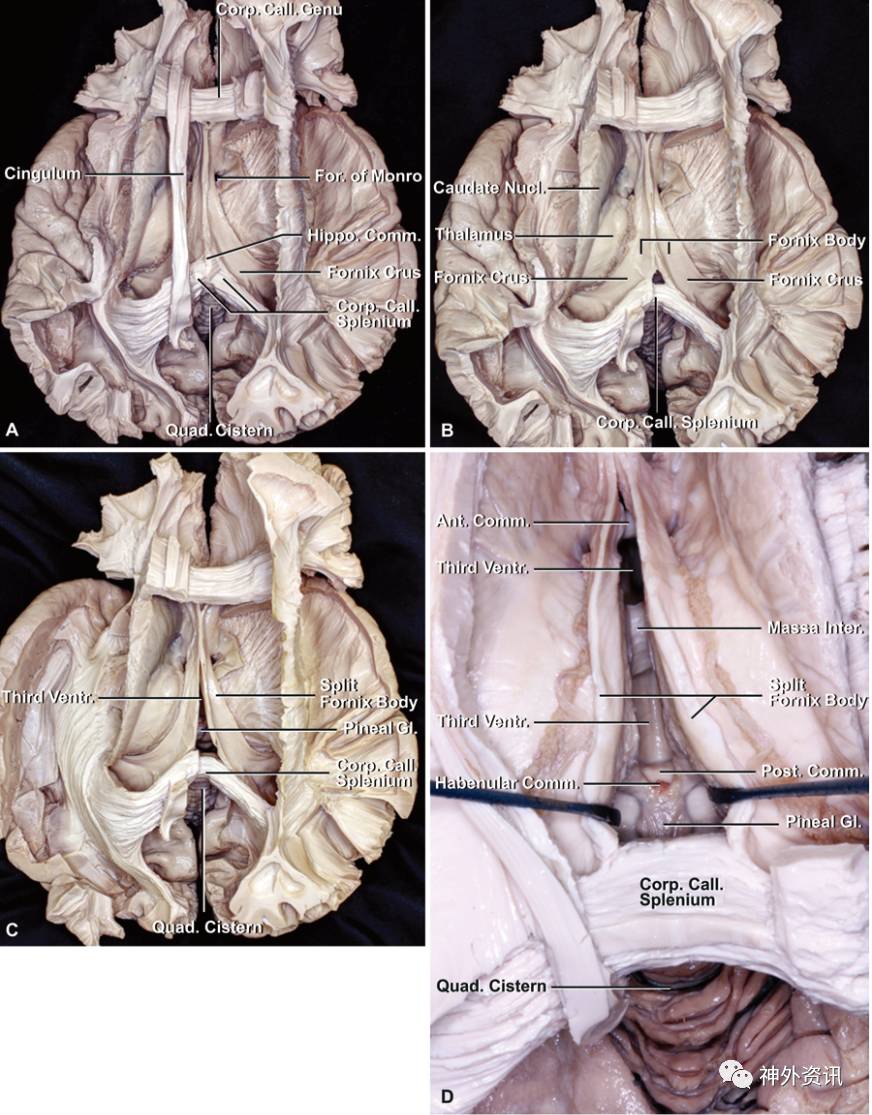

图2. A.另外一具尸头的上面观:分离并切除右侧大脑半球,暴露胼胝体和侧脑室的结构。绿色箭头所指为额部开颅经前纵裂经胼胝体压部入路的手术通道。B.后面观:大脑镰与小脑幕在镰幕交界处汇合,正好位于胼胝体压部后方。松果体区在镰幕交界处下方。C.上面观:切除胼胝体体部暴露部分侧脑室、透明隔、穹窿体和胼胝体压部。D.上面观:胼胝体构成侧脑室顶。扣带定位术中胼胝体显露的外侧界。E.切除胼胝体体部的后部和部分压部显露侧脑室内部结构。

图3. A.切除胼胝体体部暴露侧脑室,左侧扣带保留。B.切除扣带回,切开海马连合,侧脑室底由丘脑和穹窿体组成,而侧脑室外侧壁则由尾状核构成。穹隆脚在中线汇合构成穹窿体。C.切开穹窿体和海马连合暴露第三脑室和松果体区,四叠体池位于胼胝体压部下方。D.上面观:切开穹窿体和海马连合暴露第三脑室和松果体区,在胼胝体压部下方,可见松果体、后连合以及构成三脑室后壁的缰联合,同时也可显示三脑室内的前连合和中间块。